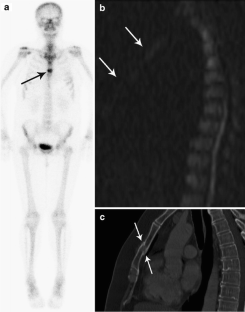

Comparison of diffusion-weighted whole body MRI and skeletal scintigraphy for the detection of bone metastases in patients with prostate or breast carcinoma

To prospectively compare the diagnostic accuracy of diffusion-weighted whole body imaging with background whole body signal suppression (DWIBS) with skeletal scintigraphy for the diagnosis and differentiation of skeletal lesions in patients suffering from prostate or breast cancer.

A diagnostic cohort of 36 patients was included in skeletal scintigraphy and 1.5 T DWIBS MRI. Based on morphology and signal intensity patterns, two readers each identified and classified independently, under blinded conditions, all lesions into three groups: (1) malignant, (2) unclear if malignant or benign and (3) benign. Finally, for the definition of the gold standard all available imaging techniques and follow-up over a minimum of 6 months were considered.

Results

Overall, 45 circumscribed bone metastases and 107 benign lesions were found. DWIBS performed significantly better in detecting malignant skeletal lesions in patients with more than 10 lesions (sensitivity: 0.97/0.91) compared to skeletal scintigraphy (sensitivity: 0.48/0.42). No statistical difference could be found between DWIBS (0.58/0.33) and skeletal scintigraphy (0.67/0.58) in the sensitivity values for malignant skeletal lesions in patients with less than 5 lesions. For benign lesions, scintigraphy scored best with a sensitivity of 0.93/0.87 compared to 0.20/0.13 for DWIBS. Interobserver agreement with Cohen’s kappa coefficient was calculated as 0.784 in the case of scintigraphy and 0.663 for DWIBS.

Conclusion

With respect to staging, in prostate and breast carcinoma, the DWIBS technique is not superior to skeletal scintigraphy, but ranks equally. However, in the cases with many bone lesions, markedly more metastases could be discovered using the DWIBS technique than skeletal scintigraphy.